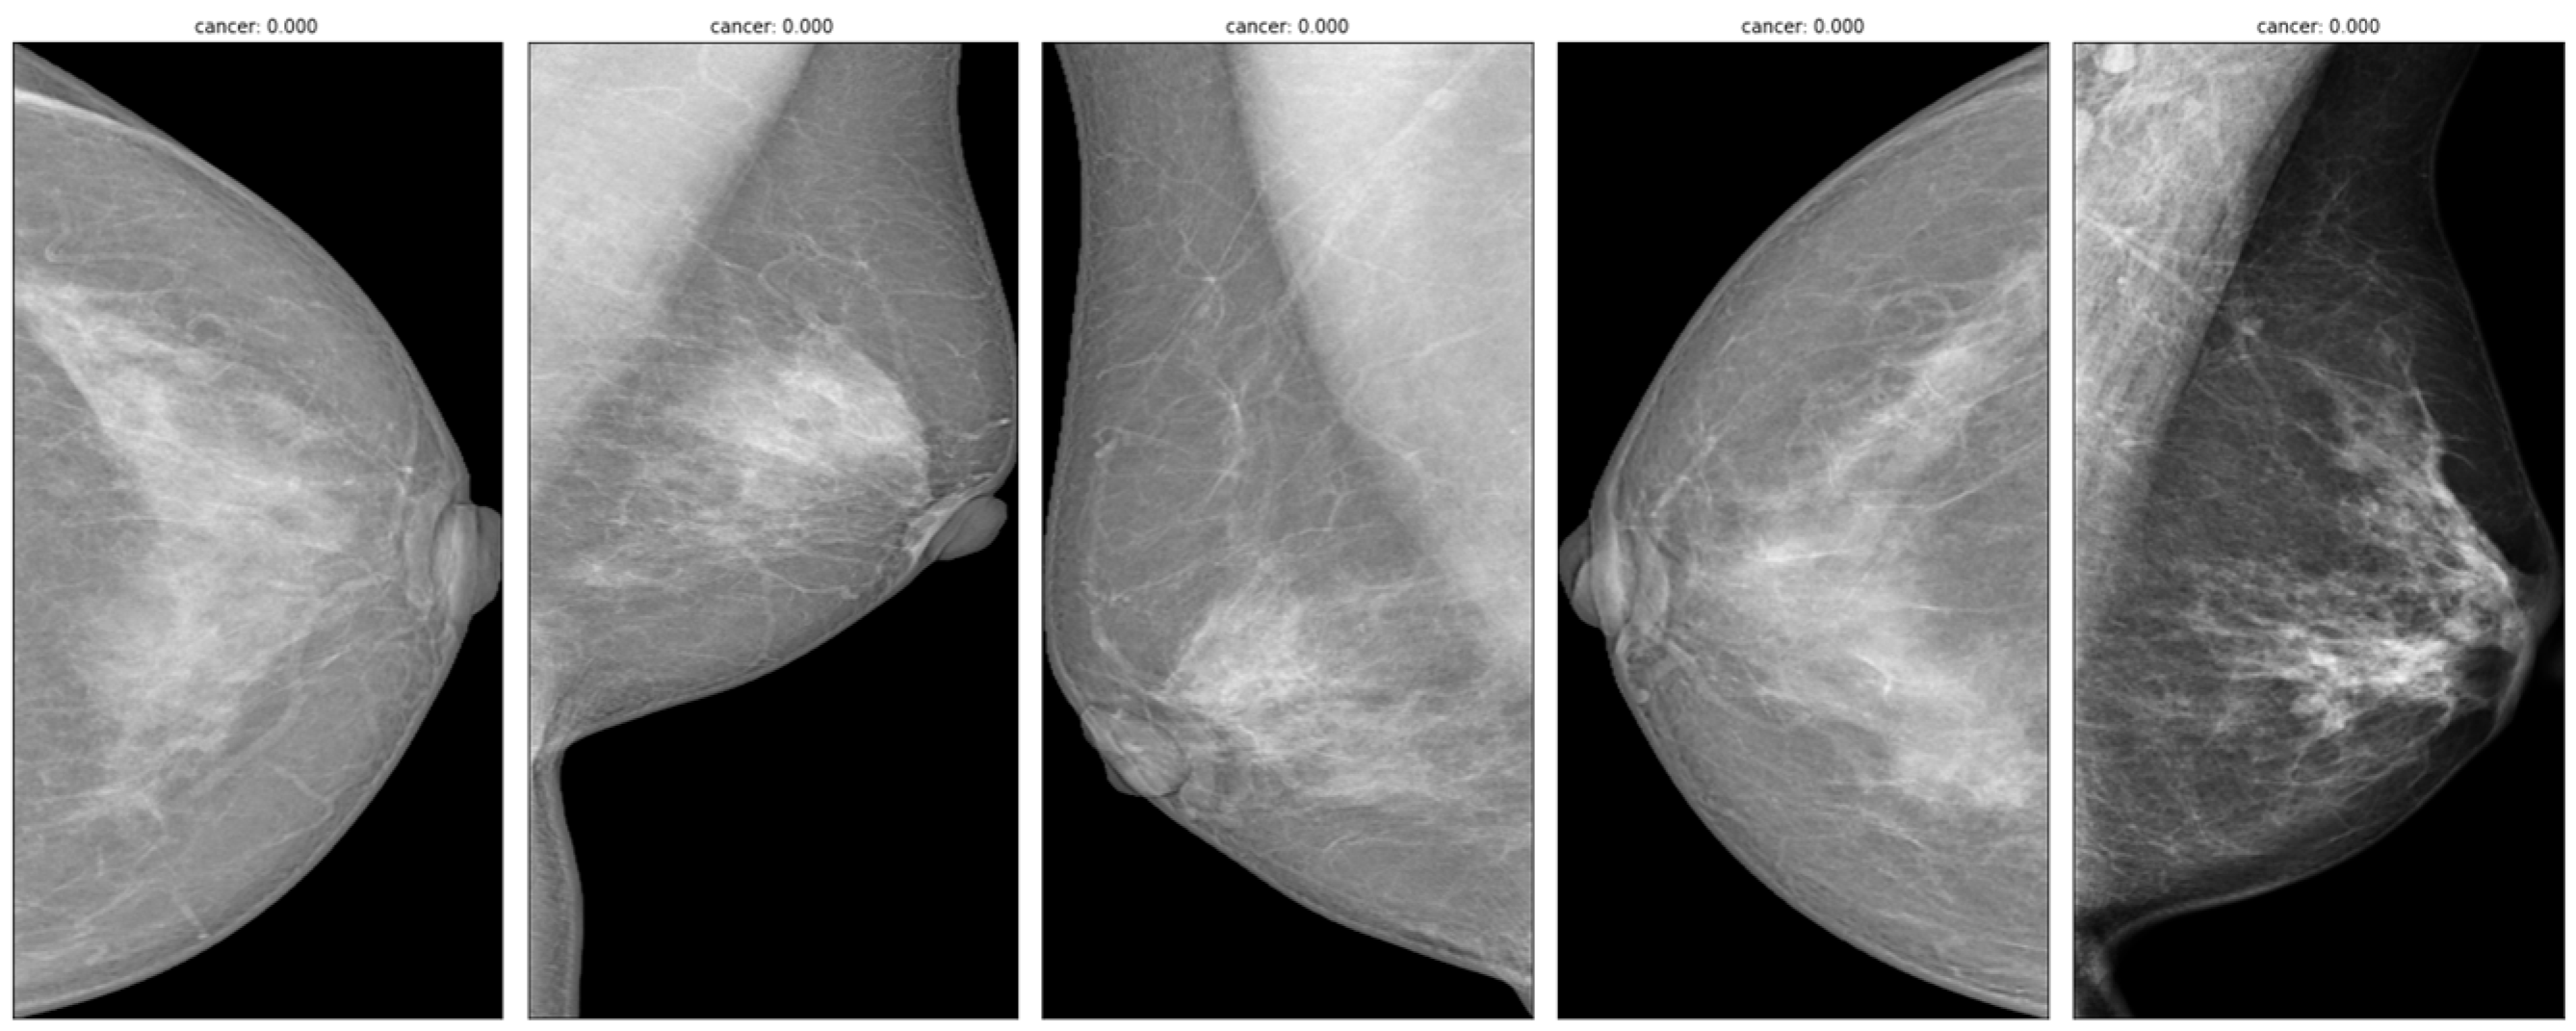

With the RSNA Mammography Data, a deep learning approach was built and evaluated for breast cancer detection and diagnosis [3]. The RSNA Mammography Data are a large-scale collection of screening mammograms from Australia and the U.S. with detailed labels, radiologists’ evaluations, and follow-up pathology results for suspected malignancies. The RSNA is a nonprofit organization that represents 31 radiology institutions in 145 different nations. Through education, research, and technological innovation programs, the RSNA strives to improve the quality of health care for patients [4]. The RSNA Mammography Data cover various mammography images with variable quality and appearance due to different factors such as acquisition parameters, compression levels, and breast density. The Breast Imaging Reporting and Data System (BI-RADS) lexicon is the main communication tool in mammography reports in most nations with established breast cancer screening programs [5]. The BI-RADS lexicon categorizes breast imaging findings into seven categories, from BI-RADS 0 (incomplete) to BI-RADS 6 (known biopsy-proven malignancy) [4]. The RSNA Mammography Data also provide information on breast density, lesion type, lesion size, lesion location, and histologic diagnosis. Figure 1 shows an example of images from the dataset.

Figure 1.

Example of mammography images from RSNA Mammography Data.